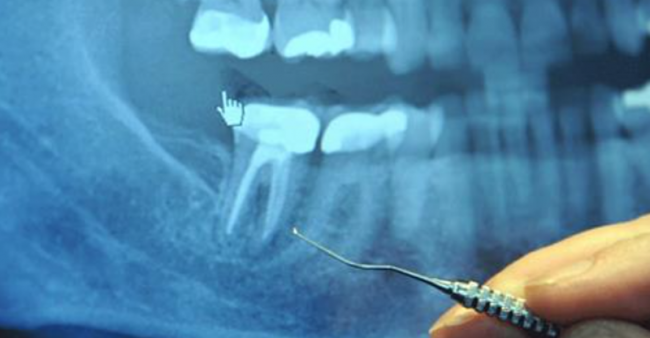

More than 25 million root canals are performed every year in this country.

Root-canaled teeth are essentially “dead” teeth that can become silent incubators for highly toxic anaerobic bacteria that can, under certain conditions, make their way into your bloodstream to cause a number of serious medical conditions—many not appearing until decades later.

Most of these toxic teeth feel and look fine for many years, which make their role in systemic disease even harder to trace back.

When a dentist performs a root canal, he or she hollows out the tooth, then fills the hollow chamber with a substance (called guttapercha), which cuts off the tooth from its blood supply, so fluid can no longer circulate through the tooth. But the maze of tiny tubules remains. And bacteria, cut off from their food supply, hide out in these tunnels where they are remarkably safe from antibiotics and your own body’s immune defenses.

No amount of sterilization has been found effective in reaching these tubules—and just about every single root-canaled tooth has been found colonized by these bacteria, especially around the apex and in the periodontal ligament. Oftentimes, the infection extends down into the jawbone where it creates cavitations—areas of necrotic tissue in the jawbone itself.